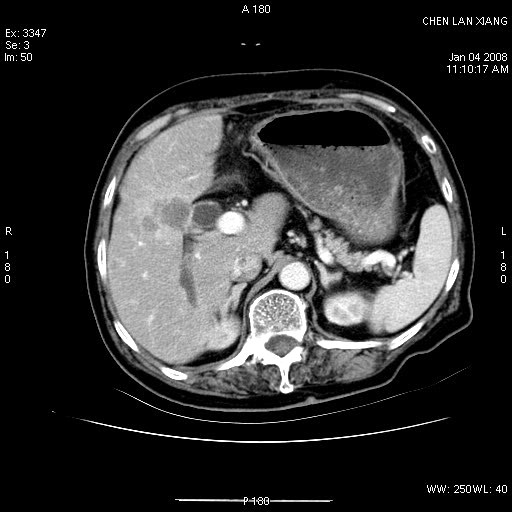

女,76岁,腹痛3-4天,b超示:肝内实性肿物,胆囊强回声,胆总管扩张.

胆囊密度增高,增强后周边肝组织及胆囊窝下部周边软组织延时性不规则强化.然胆囊壁未见明显不规则增厚及肿块.左侧肝内胆管及胆总管下段结石伴胆系扩张.

考虑;胆囊炎(黄色肉芽肿性胆囊炎?),左侧肝内胆管及胆总管下段结石.

ct所见:1、 肝内胆管结石,肝内外胆管扩张。低位胆道梗阻,胆总管下端结石;2 胆囊扩大,胆囊壁不规则增厚

考虑:胆总管下端结石并肝内外胆管扩张,肝内胆管结石;

1)胆囊癌伴肝脏转移。2)胆总管下端结石、肝内胆管结石伴肝内外胆管扩张。